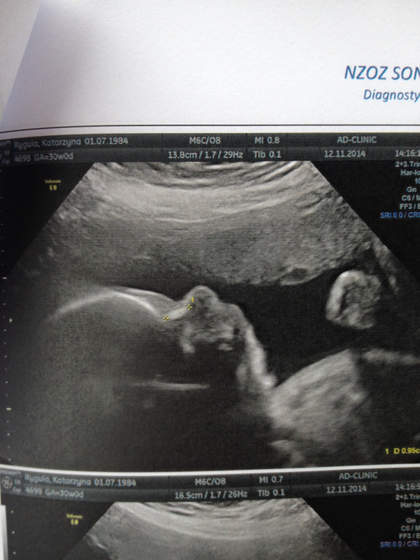

Werczita ma się dobrze. Ze złych wieści to tylko fakt, że dalej ułożona jest miednicowo. Nogi skrzyżowane ma, a stopy leżą na moim pęcherzu. Ze względu na ułożenie nóżek, lekarz nie był w stanie odczytać płci :)

Mała wazy 1473 g, więc wielkoludem nie bedzie. Ale wszystko mieści sie w normach. Data porodu z usg zgodna z OM.

A to nosek mojej Werczity